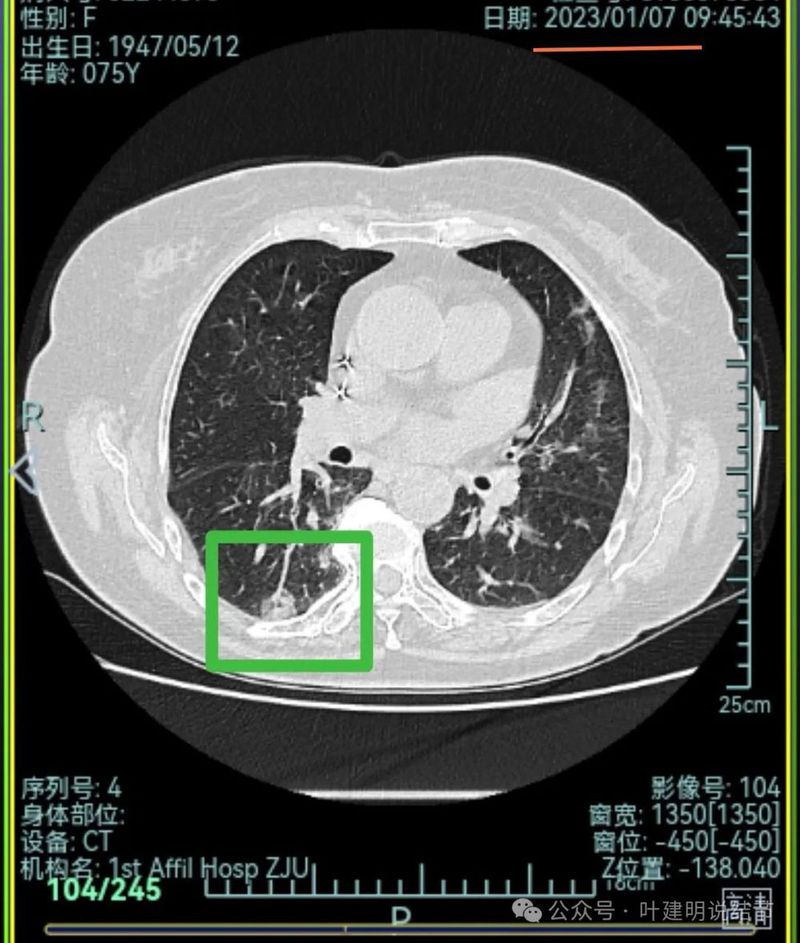

再来看2024年9月时的关键影像:

右上后段灶病灶不单没有好转,灶内密度是有增加进展的!

中叶处病灶不见了。

下叶背段伴血管征的病灶也不见了。

现在的影像考虑:

不单是右中叶以及右下叶的病灶吸收消失了,两肺其他病灶也基本上都不见了,唯独右上后段的病灶仍在而且有进展!再加上此灶原来单看也像恶性的,所以这位结友是感染与肿瘤并存,右上病灶基本上肯定是恶性的,而且是浸润性腺癌。